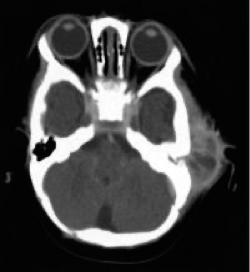

Investigation mastoid abcess

- CT scan of temporal bones